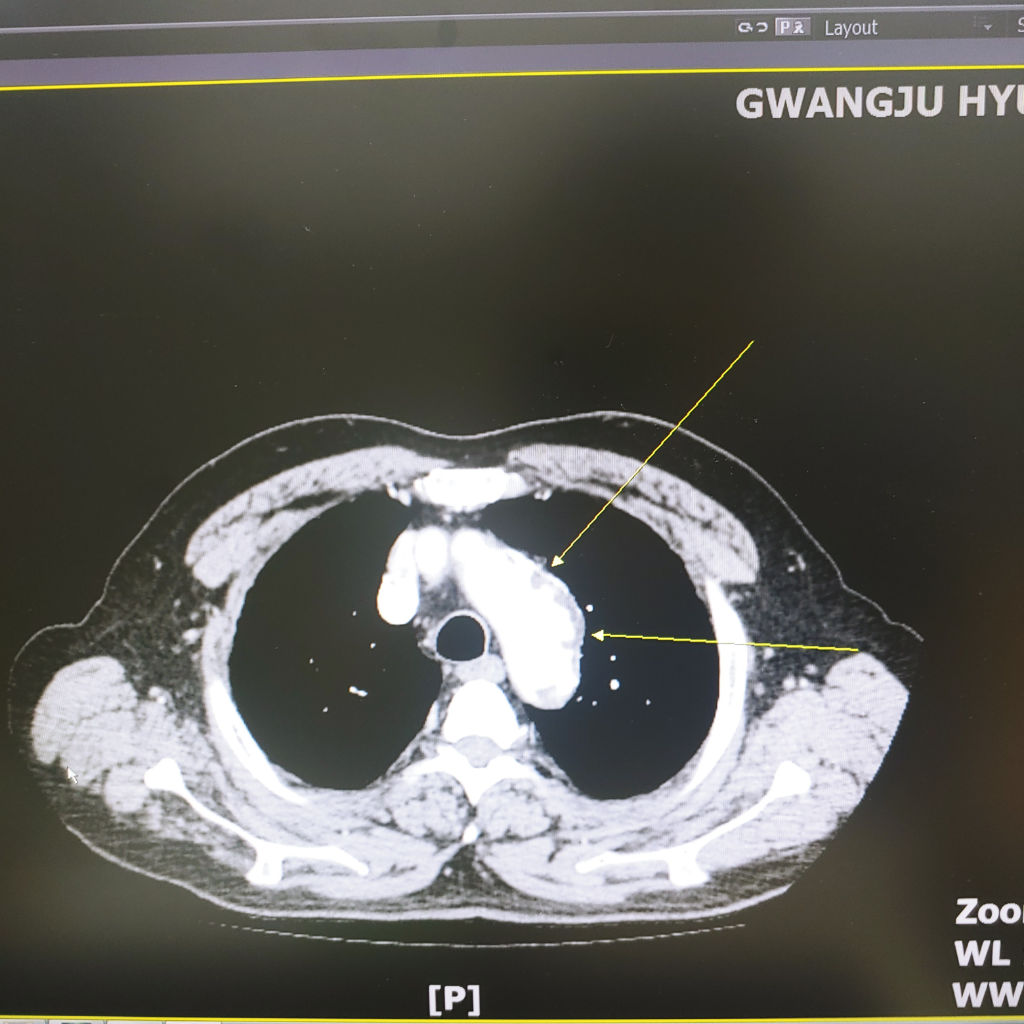

대동맥궁에 동맥류가 있다고 씨티판독에 나오는데 어떤가요?

아버지가 검진으로 씨티 조영제 사용 촬영했는데

대동맥궁에 동맥류가 있다는데 이거 위험한건가요?

사진첨부합니다

• 올리신 CT 사진의 소견을 보았을 때에 동맥류의 가능성이 매우 높아 보이는 것이 맞습니다. 대동맥류로 인해서 혈관의 직경이 커져 있는 상태인데 이것이 만약 지속적으로 커지게 될 경우 추후에 파열이 되어 치명적인 상태까지 이어질 수 있습니다. 보통은 하행대동맥에 많이 생기는데 대동맥궁에 생긴 것이라면 위험도가 더 클 수 있습니다. 다만 해당 사진 한 장만 보고 이렇다 저렇다 자세하게 알 수는 없기 때문에 관련하여서는 주치의 선생님께 자세하게 설명을 들어보시는 것이 좋겠습니다.